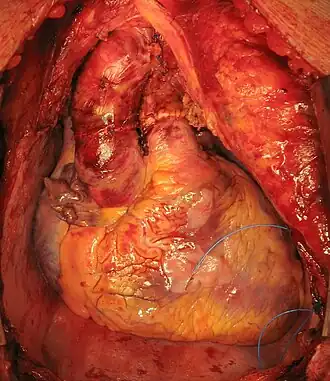

Harttransplantatie

Een harttransplantatie is een medische ingreep waarbij het hart van een (overleden) donor wordt geplaatst (transplantatie) in een patiënt wiens hart niet meer in staat is om de patiënt in leven te houden. Na een succesvolle transplantatie had een patiënt met een ruilhart (of donorhart) op basis van statistieken uit 2007 een gemiddelde levensverwachting van nog ongeveer 15 jaar.[1]